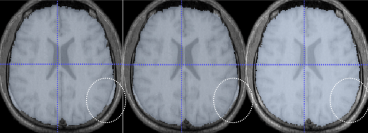

Mindboggle (mindboggle.info) is open-source software for the analysis (feature extraction, labeling, and morphometry) of human brain imaging data. Features include anatomical regions (like gyri and subcortical regions), sulcal folds, and fundus curves. Shape measures include two types of depth, two types of curvature, volume, thickness, Zernike moments, Laplace-Beltrami spectra, etc. The project has been funded by three NIH grants, and is maintained by the Computational Neuroimaging Lab at the Child Mind Institute.

A Klein, SS Ghosh, B Avants, BTT Yeo, B Fischl, B Ardekani, JC Gee, JJ Mann, RV Parsey. Evaluation of volume-based and surface-based brain image registration methods. NeuroImage. 51: 214-220 (2010). PMCID: PMC2862732.

A Klein, J Andersson, BA Ardekani, J Ashburner, B Avants, M-C Chiang, GE Christensen, DL Collins, J Gee, P Hellier, JH Song, M Jenkinson, C Lepage, D Rueckert, P Thompson, T Vercauteren, RP Woods, JJ Mann, RV Parsey. Evaluation of 14 nonlinear deformation algorithms applied to human brain MRI registration. NeuroImage. 46(3): 786-802 (2009). PMCID: PMC2747506. Data.